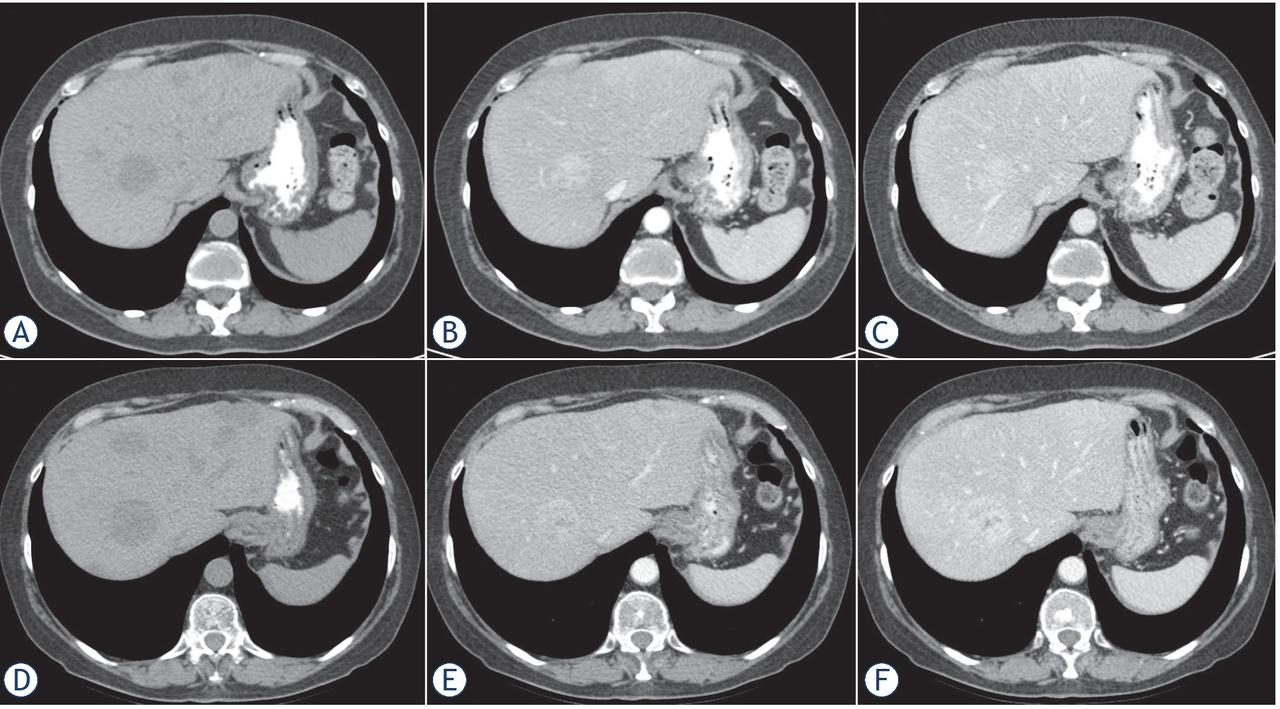

Figure 1